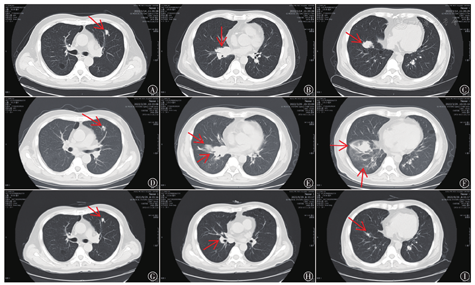

患者男,54岁,因"体检发现右肾占位8 d"2020年7月3日就诊于安徽医科大学第一附属医院泌尿外科,既往吸烟史30年。完善检查排除禁忌后于2020年7月9日在全麻下行腹腔镜下右肾癌根治术。病理诊断:(右肾)透明细胞性肾细胞癌,肾细胞癌WHO/ISUP核分级标准:3~4级;免疫组织化学结果显示:Ki-67(+,10%~15%),CKPAN(+),CK7(-),VIM(-),CD10(+),RCC(+,灶性),CAIX(+)。术后诊断为右肾透明细胞癌,T1bN0M0 Ⅰ期,肾癌UISS预后分级系统划分为中危。2021年11月4日患者复查胸、腹部CT示:右肾术后改变,双肺多发软组织结节影,最大长径约27.3 mm,考虑转移瘤。2021年11月5日转入本院中西医结合肿瘤科后患者拒行经皮肺穿刺活检术,临床诊断为肾癌术后双肺多发转移,国际转移性肾癌数据库联盟(IMDC)晚期肾癌预后模型及纪念斯隆凯特琳癌症中心(MSKCC)晚期肾癌预后模型均评为中危,予以培唑帕尼(英国葛兰素史克公司,批号:H20170062,规格:200 mg/片;400 mg/次,口服,1次/d)治疗。2021年12月10日胸、腹部CT提示右肺中叶转移瘤较前增大,最大长径约30.0 mm,评估病情进展,排除禁忌证后,予以培唑帕尼(800 mg/次,口服,1次/d)治疗。2022年1月16日胸、腹部CT提示双肺病灶稍缩小,最大长径约26.0 mm,考虑治疗有效,继续给予培唑帕尼(800 mg/次,口服,1次/d)治疗。2022年3月14日胸、腹部CT提示两肺转移灶、纵隔及右肺门淋巴结明显增大,最大长径约32.2 mm(见图1A~C),考虑酪氨酸激酶抑制剂(tyrosine kinase inhibitor,TKI)治疗失败,转为二线帕博利珠单抗(美国默沙东公司,批号:S20180019,规格:100 mg/瓶;200 mg/次,静脉滴注,第1天;21 d为1周期)联合阿昔替尼(美国辉瑞公司,批号:H20150221,规格:5 mg/片;5 mg/次,口服,2次/d)治疗。2022年3月29日患者出现呼吸短促、胸闷,活动后加重,同时伴有咳嗽咳痰及间断发热,入院查体:脉搏94次/min、呼吸23次/min、血压136/84 mmHg(1 mmHg=0.133 kPa)、指脉氧93%~96%,双肺呼吸音低,右肺可闻及干湿性啰音;胸部CT提示两肺纹理增多、增粗,两肺散在囊状无肺纹理透亮区,双肺转移灶增大,最大长径约34.1 mm,右肺中下叶见斑片状、纤维索条影等高密度影改变(见图1D~F);肺功能提示轻度非特异性通气功能障碍,小气道功能轻度异常;心脏超声提示左室顺应性下降;支气管镜下肺泡灌洗提示肺泡淋巴细胞存在异常聚集;结合既往病史,排除病灶进展、心衰、肺部感染,考虑免疫检查点抑制剂(immune checkpoint inhibitor,ICI)相关性肺炎(immune checkpoint inhibitor-related pneumonitis,CIP),根据《中国临床肿瘤学会(CSCO)免疫检查点抑制剂相关的毒性管理指南2021》[1]分级为G2,给予甲泼尼龙(美国辉瑞公司,批号:JX20160069,规格40 mg/瓶;60 mg/次,静脉滴注,1次/d,第1~3天)治疗,患者症状有所改善后减量为40 mg/次(静脉滴注,1次/d,第4~7天),然后改为泼尼松片(山东鲁抗医药集团赛特有限责任公司,批号:H20033023,规格:5 mg/片;40 mg/次,口服,1次/d,持续1周),后续每周递减10 mg剂量,最后1周为泼尼松片5 mg/次(口服,1次/d,持续1周),激素治疗总疗程为6周,期间单药阿昔替尼(5 mg/次,口服,2次/d)治疗,患者症状明显改善。2022年4月25日复查胸、腹部CT提示右肺病灶缩小,最大长径约21.82 mm;右肺下叶间质性改变明显减少,表明既往使用帕博利珠单抗联合阿昔替尼治疗有效,考虑到重启相同种类ICI,CIP复发概率可能更高,故改用恩沃利单抗(江苏康宁杰瑞生物制药有限公司,批号:S20210046,规格:200 mg/瓶;400 mg/次,皮下注射,第1天;21 d为1周期)联合阿昔替尼(5 mg/次,口服,2次/d)治疗。2个疗程后复查胸、腹部CT提示双肺病灶、纵隔内淋巴结较前明显缩小,最大长径约10.05 mm,维持原方案治疗。4个周期后复查胸部CT评估病灶及纵隔内淋巴结大小较前相仿,最大长径约9.60 mm,考虑病情稳定,继续使用原方案治疗。6个周期后复查胸部CT提示:双肺部分病灶、纵隔内淋巴结再次变小,最大长径约8.26 mm(见图1G~I),提示治疗有效。患者继续使用恩沃利单抗联合阿昔替尼治疗,末次随访至2023年2月16日,期间复查心脏超声、心肌酶谱、甲状腺及肝肾功能未见异常,无明显皮疹、腹泻等不适;未出现CIP复发或其他免疫相关不良反应(immune-related adverse effect,irAE)。